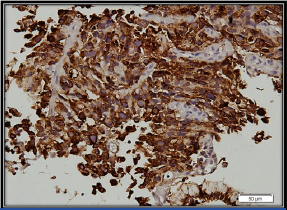

Chest x-ray showing bilateral opacities in the mid and lower lung zones.

The patient was initially managed to ensure haemodynamic stability with intravenous fluid, transfusion of three units of packed red blood cells, broad spectrum antibiotics along with other symptomatic measures. Sputum analysis for acid fast bacilli was negative and bacteriological culture was sterile. However, based on the history of contact with tuberculosis in the family, anti-tubercular therapy consisting of isoniazid, rifampicin, ethambutol and pyrazinamide was started empirically. Two-dimensional echocardiogram showed dilated right atrium and right ventricle, severe Pulmonary Arterial Hypertension (PAH) with normal left ventricular ejection fraction. Stool for occult blood was positive and a consequent upper gastro-intestinal endoscopy showed a large ulcerative growth in the lesser curvature of the stomach suggestive of carcinoma of the stomach. A HRCT scan of the thorax showed nodular thickening of interlobular septa with peribronchial cuffing and fissural thickening along with minimal right sided pleural effusion [Table/Fig-2]. The biopsy from the gastric ulcer showed poorly differentiated malignancy. On immunohistochemistry, epithelial membrane antigen showed strong membranous and cytoplasmic positivity and cytokeratin showed variable positivity, confirming its epithelial origin in favour of adenocarcinoma. CD45, CD3, CD10, CD20 were negative ruling out lymphoma. CD117, HMB 45, and synaptophysin were negative ruling out gastrointestinal stromal tumour, malignant melanoma and neuroendocrine carcinoma respectively [Table/Fig-3,4 and 5].

Tumour cells showing cytoplasmic positivity for cytokeratin Immunohistochemistry (IHC); 200X).